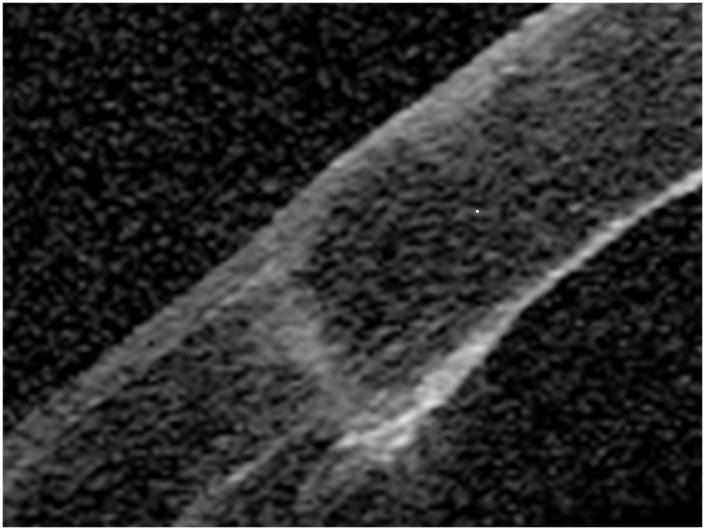

To assess the clinical outcomes of femtosecond laser-assisted keratoplasty (FLAK) using the VisuMax femtosecond laser system, and to compare them with those of conventional penetrating keratoplasty (PK).

We retrospectively examined 20 eyes of 20 consecutive patients undergoing FLAK and 20 eyes of 20 age- and diagnosis-matched patients undergoing conventional PK. We quantitatively assessed corneal astigmatism, refractive astigmatism, and corrected visual acuity, 1, 3, and 6 months postoperatively, and endothelial cell density 6 months postoperatively.

Corneal and refractive astigmatism after FLAK were significantly lower after FLAK than that after conventional PK at 3 and 6 months postoperatively (p = 0.04 and p = 0.03, respectively, Mann-Whitney U test). FLAK provided significantly faster visual recovery than conventional PK at 1 month postoperatively (p = 0.02), but not at 3 and 6 months postoperatively (p = 0.52 and p = 0.80, respectively). We found no significant differences in the change in endothelial cell density between the two groups (p = 0.30).

FLAK using the VisuMax femtosecond laser system induces significantly less corneal and refractive astigmatism than conventional PK, and provides significantly faster visual recovery in the early postoperative period, possibly because the geometry of the donor-recipient matching is more physiological and requires less tight sutures. It is suggested that FLAK has advantages over conventional PK, in terms of astigmatism and fast visual recovery.